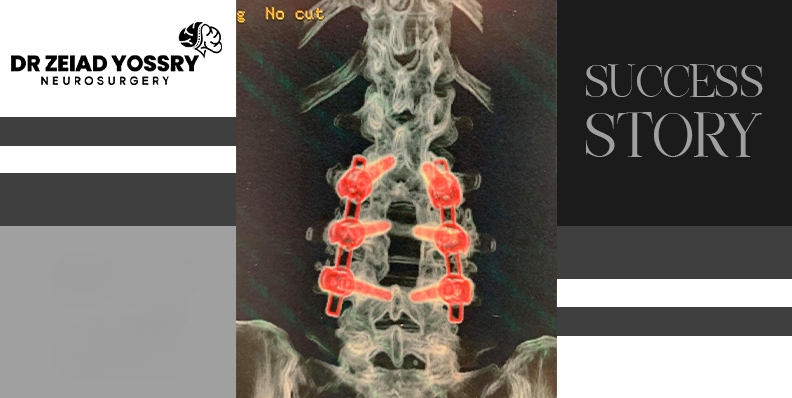

Dr. Zeiad Yossry performed a fracture stabilization surgery to limit movement between the fractured vertebrae and relieve pain. In this procedure, two or more vertebrae are joined together and held in the correct position, preventing them from moving until they have a chance to fuse. The surgery was successfully performed by using metal screws for strengthening the spine and preventing further movement at the fracture site.